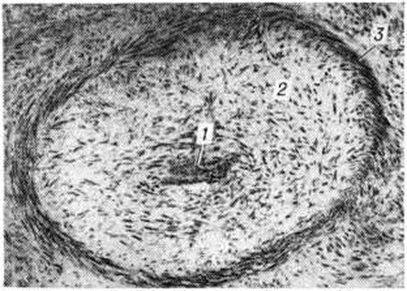

Рис. 1.

Микропрепарат мягкой оболочки головного мозга больного, погибшего от острого серозного менингита: в клеточном инфильтрате преобладают лимфоциты (1) и плазмоциты (2) × 200.

Рис. 2.

Микропрепарат головного мозга больного, погибшего от туберкулёзного менингоэнцефалита: сливающиеся эпителиоидно-клеточные гранулемы в стенке III желудочка мозга указаны стрелками; × 100.

Рис. 3.

Микропрепарат спинного мозга больного, погибшего от туберкулёзного цереброспинального лептопахименингита: 1 — белое вещество; 2 — спаянные и утолщённые оболочки спинного мозга; 3 — облитерированные сосуды; × 10.

Рис. 4.

Микропрепарат головного мозга больного, погибшего от туберкулёзного менингита (средняя мозговая артерия облитерирована): 1 — просвет артерии, 2 — утолщённая фиброзированная внутренняя оболочка артерии, 3 — мышечная оболочка артерии; × 200.